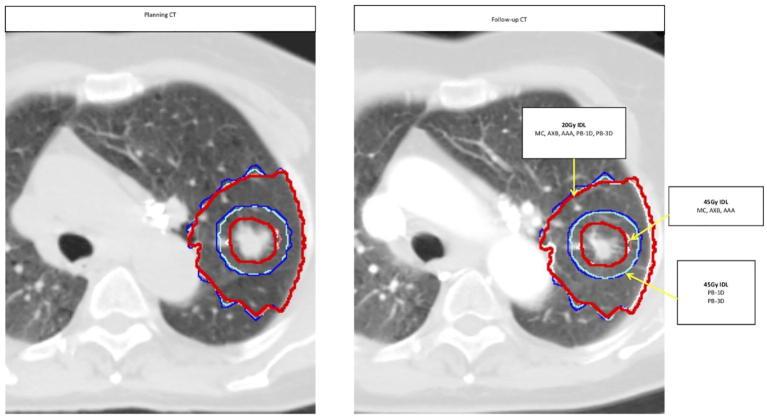

MATERIALS AND METHODS

Thirty-one patients (with a total of 33 lesions) with non-small cell lung cancer were selected out of 270 patients treated with SBRT at a single institution between 2003 and 2009. Out of these 31 patients, 10 patients had developed radiation pneumonitis (RP). Dose distributions originally planned using a 1-D pencil beam-based dose algorithm were retrospectively recomputed using different algorithms. Prescription dose was 48 Gy in 4 fractions in most patients. Planning CT images were rigidly registered to follow-up CT datasets at 3-9 months after treatment. Corresponding dose distributions were mapped from planning to follow-up CT images. Hounsfield Unit (HU) changes in lung density in individual, 5 Gy, dose bins from 5 to 45 Gy were assessed in the peri-tumoral region. Correlations between HU changes in various normal lung regions, dose indices (V20, MLD, generalized equivalent uniform dose (gEUD)), and RP grade were investigated.

Strong positive correlation was found between HU changes in the peri-tumoral region and RP grade (Spearman's r = 0.760;  < 0.001). Positive correlation was also observed between RP and HU changes in the region covered by V20 for all algorithms (Spearman's r ≥ 0.738;  < 0.001). Additionally, V20, MLD, and gEUD were significantly correlated with RP grade ( < 0.01). MLD in the peri-tumoral region computed with model-based algorithms was 5-7% lower than the PB-based methods.

CONCLUSION

Changes of lung density in the peri-tumoral lung and in the region covered by V20 were strongly associated with RP grade. Relative to model-based methods, PB algorithms over-estimated mean peri-tumoral dose and showed displacement of the high-dose region, which correlated with HU changes on follow-up CT scans.